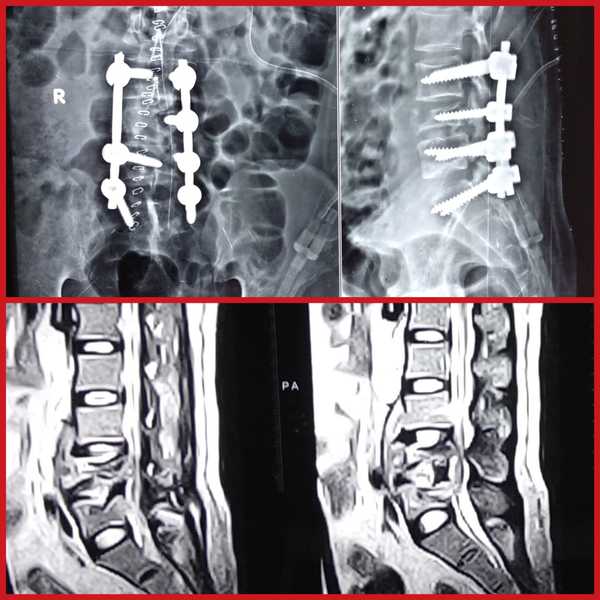

SPINE SURGERY SPECIALIST IN PIMPLE SAUDAGAR, WAKAD...

Dr. Rahul Chaudhari Pimple Saudagar, PCMC [ MBBS M...